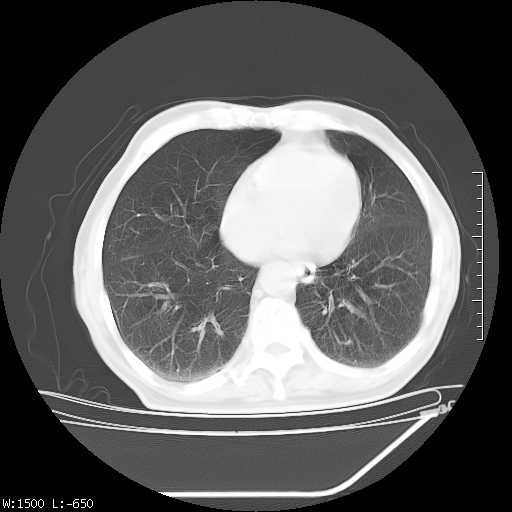

标题: CT23994:男、72、咳嗽、气短两月余,近来消瘦。 [打印本页]

标题: CT23994:男、72、咳嗽、气短两月余,近来消瘦。

tb可能性大(双肺均可见片状密度增高灶,其内可见低密度空洞)。

右上肺大片状密度增高影,与胸膜关系密切,内见低密度透亮影,胸膜下可见三角形不张影,左下肺沿支气管走形结节影,纵膈内淋巴结显示。考虑结核并疤痕性不张可能性大,建议穿刺活检,排除肺泡癌。